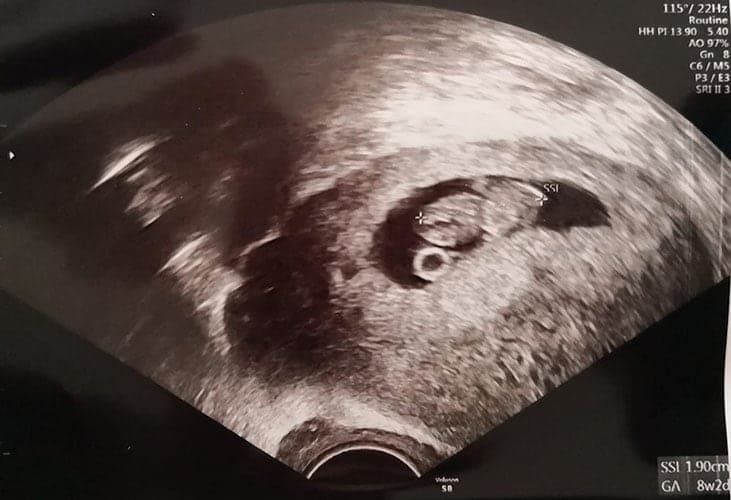

Ultraschallbilder aus dem 1. Trimester (1. SSW bis 12. SSW)

Im ersten Trimester sind die Ultraschallbilder meist noch schwer zu deuten. Oft erkennt man in den letzen Wochen des ersten Trimesters gut den Körper, den Kopf und die Gliedmaße. Das Geschlecht kann man in dieser Zeit meist noch nicht erkennen.